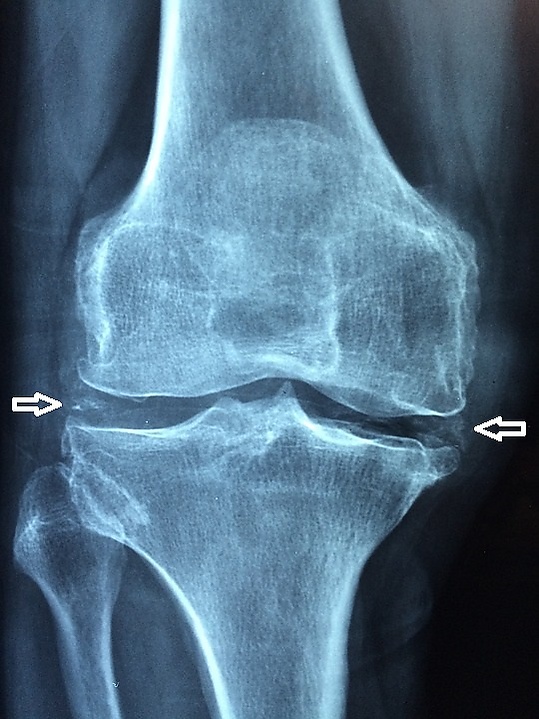

Основана на обнаружении в синовиальной жидкости кристаллов со слабоположительным светопреломлением внутри нейтрофилов или вне клеток с сопутствующим нейтрофилезом. Рентгенологически обнаруживается хондрокальциноз — кальцификация суставного хряща (наиболее часто в менисках, межпозвоночных дисках), синовиальной мембраны и сухожилий; также характерны остеоартрические изменения в нетипичных для остеоартрита суставах (лучезапястных, локтевых, плечевых, пястно-фаланговых); возможно выявление субхондральных кист и крючкообразных остеофитов[4].